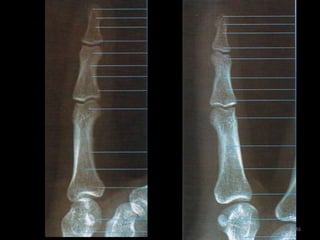

Incidência PA ou AP dos dedos da mão 138

139

140

Incidência lateral (lateral-medial ou médio-lateral) dos dedos141

142

143